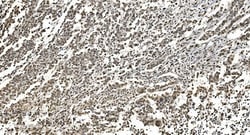

Adding 0.2 mL of distilled water will yield a concentration of 500 μg/mL. Positive Control - WB: human Jurkat whole cell, human PC-3 whole cell, human Raji whole cell, human K562 whole cell, human Caco-2 whole cell, human MCF-7 whole cell, human HL-60 whole cell, human PC-3 whole cell. IHC: human breast cancer tissue, human gastric cancer lymph node tissue, human liver cancer tissue, human ovarian serous adenocarcinoma tissue, human pancreatic cancer tissue, human placenta tissue, human rectal cancer tissue. ICC/IF: MCF-7 cell. Flow: K562 cell. Store at -20°C for one year from date of receipt. After reconstitution, at 4°C for one month. It can also be aliquotted and stored frozen at -20°C for six months. Avoid repeated freeze-thaw cycles.

| Applications | ELISA, Flow Cytometry, Immunohistochemistry (Paraffin), Western Blot, Immunocytochemistry |